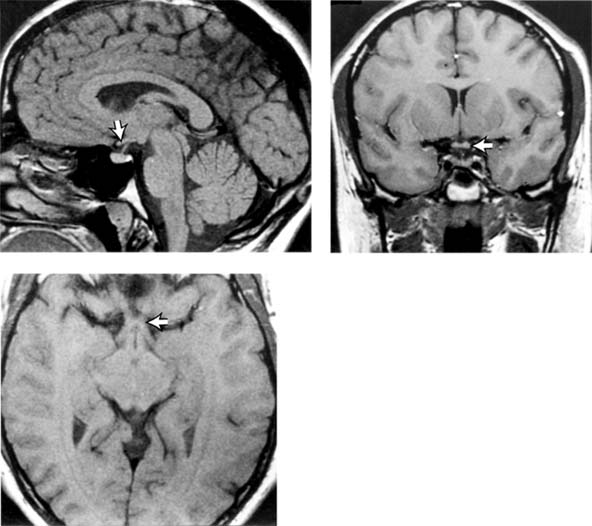

Figure 14-1

Figure 14-1: Magnetic resonance imaging (MRI) of normal brain in sagittal section (upper left), coronal section (upper right), and axial section (lower left). The white arrows indicate the chiasm.

Intracranially, the two optic nerves join to form the optic chiasm (Figure 14-1). At the chiasm, more than half of the fibers (those from the nasal half of the retina) decussate and join the uncrossed temporal fibers of the opposite nerve to form the optic tracts. Each optic tract sweeps around the cerebral peduncle toward the lateral geniculate nucleus, where it will synapse. All of the fibers receiving impulses from the right hemifields of each eye thus make up the left optic tract and project to the left cerebral hemisphere. Similarly, the left hemifields project to the right cerebral hemisphere. Twenty percent of the fibers in the tract subserve pupillary function. These fibers leave the tract just anterior to the nucleus and pass via the brachium of the superior colliculus to the midbrain pretectal nucleus. The remaining fibers synapse in the lateral geniculate nucleus. The cell bodies of this structure give rise to the geniculocalcarine tract. This tract passes through the posterior limb of the internal capsule and then fans into the optic radiations that traverse parts of the temporal and parietal lobes en route to the occipital cortex (calcarine, striate, or primary visual cortex).